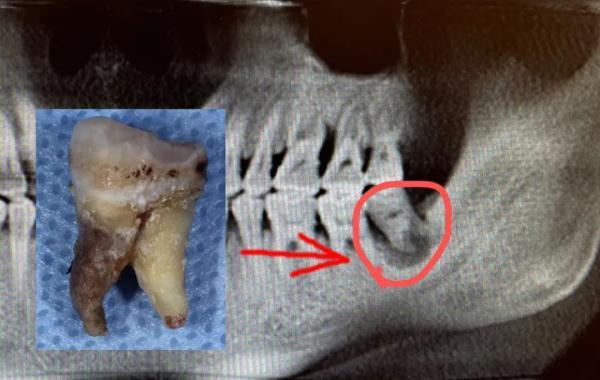

陳申國說,這么嚴(yán)重的感染,一般要兩個(gè)星期才能恢復(fù),蔣先生的身體確實(shí)好,才一個(gè)多星期,病灶處的膿液已經(jīng)排得差不多了,可以拔除那顆病牙了。

問題牙齒